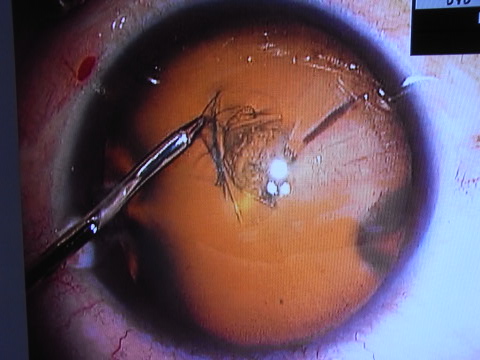

2.水晶体の前嚢という皮をめくるCCCという手技があるのですが、この手技の安全性を高めるために「池田式CCCセッシ」という、小さな傷から挿入できる器具を全例に採用した。(この器具は非常に高価なためほとんどの公立病院では保有していても数本であり、全例に採用している施設はまだ稀だと思います。)

この器具を使ってどのようにその前嚢をめくるのか、一例を下にお示しします。左側に見えている器具がその池田式CCCセッシです。

丸く、皮がめくれているのがお分かり頂けると思います。